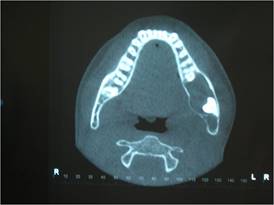

Para una mejor evaluación de la extensión de la lesión, se solicitó una tomografía volumétrica de haz cónico de la región, donde se pudo observar sus límites y relaciones anatómicas circundantes (Fig. 2).

Confrontando la anamnesis, el examen físico y los exámenes complementarios, se estableció la hipótesis diagnóstica de quiste dentígero, ameloblastoma o queratoquiste odontogénico. El tratamiento propuesto y aceptado por los responsables luego de leer, concordar y firmar el Formulario de Consentimiento Libre e Informado (FCLI), fue realizar una biopsia de marsupialización bajo anestesia general, con el propósito de diagnosticar y descomprimir la lesión (como terapéutica de retraso). Luego de solicitar los exámenes preoperatorios de rutina, que estaban dentro del estándar normal, se programó la cirugía.